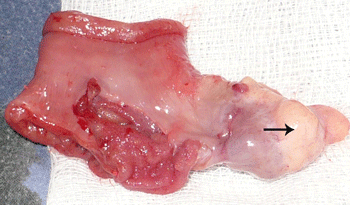

A 2-year-old girl presented with one day history of abdominal distension, bilious vomiting and not passing stool. There was no preceding history of significant illness. The patient was vitally stable. Abdomen was distended with tenderness on right side. Digital rectal examination revealed an empty rectum. Abdominal radiograph showed air fluid levels. Ultrasound of abdomen gave an impression of intussusception. Laboratory investigations were within normal limits. Patient was managed with intravenous fluids, prophylactic antibiotics, nasogastric decompression, and analgesics. Exploratory laparotomy was performed within 3 hours of presentation that revealed an ileoileal intussusception which was manually reduced. A polyp like pedunculated growth was palpable at about 30 cm proximal to ileocecal valve. An enterotomy was performed for polypectomy; however, the pedunculated growth had a pale tissue at the tip giving a suspicion of heterotopic tissue (Fig. 1). The involved segment of the ileum was resected and end to end hand sewn anastomosis was performed. The polypoid growth was inspected carefully and with a suspicion of inverted Meckel's diverticulum, reduced back confirming the diagnosis (Fig. 2). The patient had an uneventful recovery. She remained well at one year follow-up (1 year). Histopathology of the specimen revealed ectopic pancreatic tissue in the inverted Meckel's diverticulum.

Figure 1: The specimen after resection showing a pedunculated polyp like growth with an ectopic tissue at the tip (arrow). |